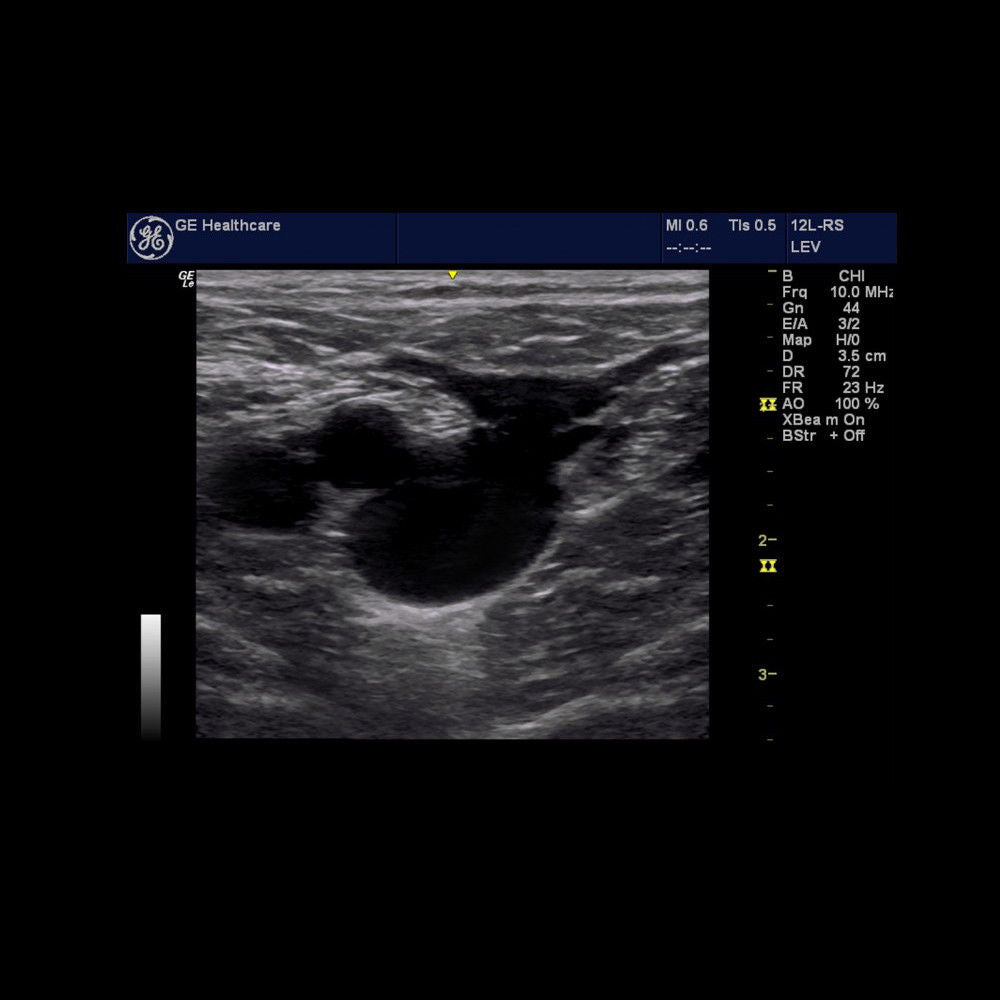

Seller Notes:âGreat Condition!! - Manufacturer (GE) Refurbished!!â

Brand: LOGIQ E